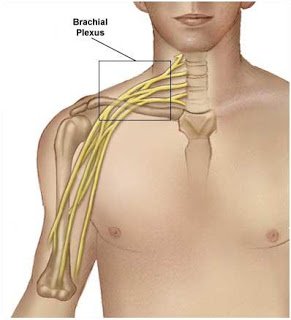

2. Sinir zedelenmeleri: Vidaların seyri boyunca sinirde bacağa giden sinirlerde meydana gelen zararlanmalar.Seviyeye göre değişmek

üzere motor ve duyu arazları gelişebilir.